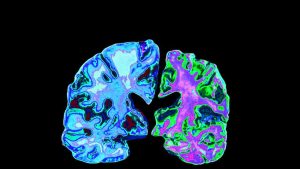

The Future Of Alzheimer’s Treatment

The fight to cure Alzheimer’s has been a long and arduous one for countless scientists dedicated to creating drugs that slow mental deterioration and extend quality of life for those afflicted. Currently there are a number of drugs, at various states of their clinical trial evolution, attempting to make their way down the chain to eventual FDA approval.